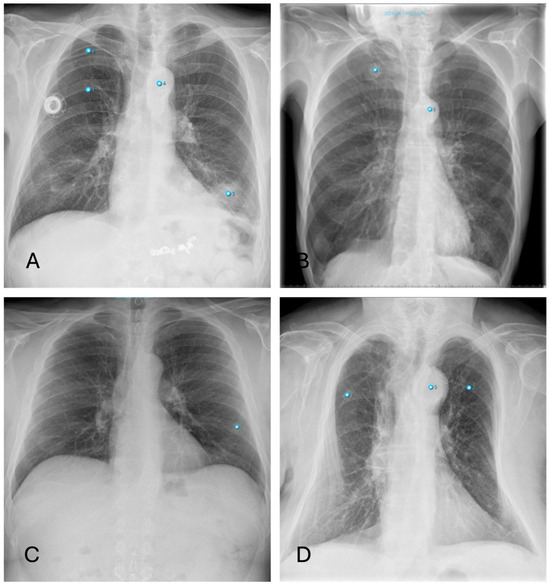

3.4.4. Pleural Effusions

Differences in the diagnosis of pleural effusion can be explained as follows: Small amounts of a pleural effusion are best identified as a dorsal costophrenic angle effusion in the lateral projection. However, AI primarily uses the PA projection for diagnosis, which means that smaller amounts of effusion might be overlooked (Figure 8).

Figure 8. Inconsistencies of pleural effusion diagnoses: (A,B)—AI missing the sulcal effusion described by the radiologist based on the lateral projection; (C,D)—Similar case with an even more prominent pleural effusion not detected by AI (Note: other findings incorrectly labelling “aortic abnormality”, “pneumonia” and “rib fracture”).